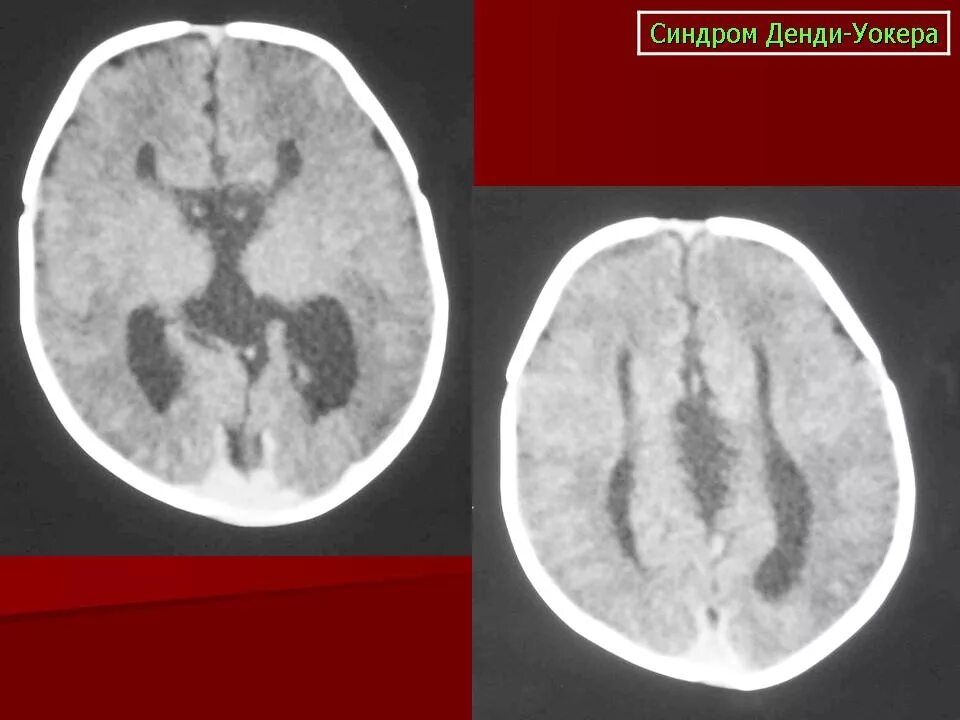

Денди уокера мрт